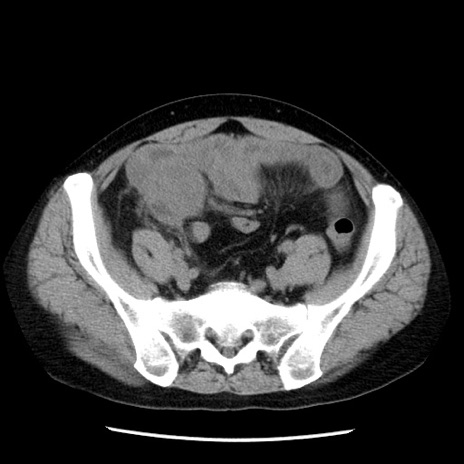

症例29(横断像)

【症例】40歳代男性

【現病歴】2日前から胃痛あり。徐々に周期的な激痛に変化した。本日になっても激痛があるため受診。

【身体所見】意識清明、BT 38-39℃台あり、腹部:膨満、やや硬、右下腹部に圧痛あり。

【データ】WBC 8500、CRP 23.26